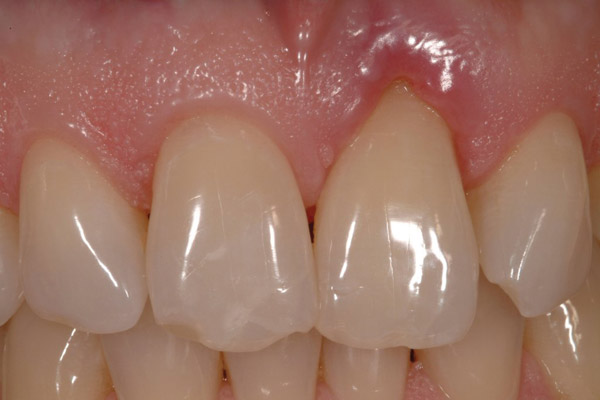

Figure 18  Periapical radiographs of the final implants show good bone levels and interproximal spacing between the implants and adjacent teeth.

Figure 18

Figure 19  The post-implantation and post-restoration view shows esthetically pleasing, symmetric crowns and mucosal contours, with the Nos. 7 and 10 implant prostheses blending in imperceptibly with the natural dentition. Restoration courtesy of Dr. Jeffrey Warren.

Figure 19